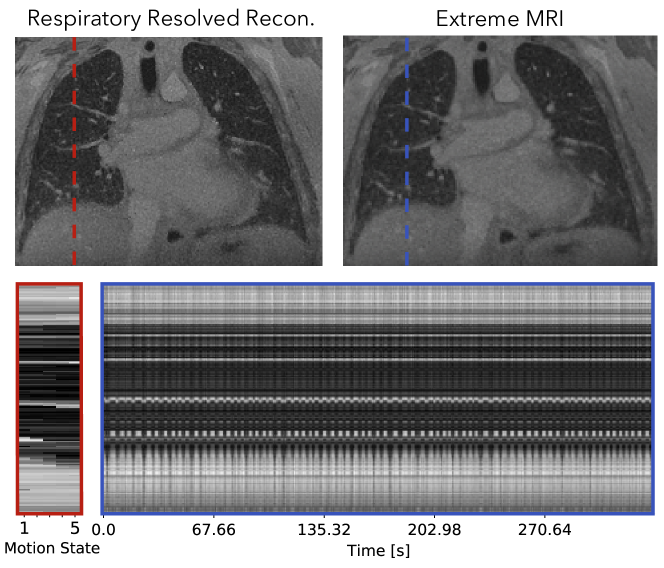

We applied the proposed reconstruction on two lung datasets from adult patients to qualitatively evaluate its performance. All datasets were acquired on GE 3T Discovery MR750 clinical scanners (GE Healthcare, Waukesha, WI) using an optimized UTE sequence [1] and a bit-reversed ordered 3D radial trajectory. The first dataset has regular respiratory motion and little bulk motion. The second dataset has abrupt bulk motions such as coughing throughout the scan.

We compared the proposed method with respiratory resolved reconstruction to five motion states. The proposed technique was reconstructed with 500 frames, whereas for the third lung dataset. The respiratory resolved reconstruction was performed with total variation regularization along the motion states, which is similar to Jiang et al. [2] and Feng et al. [54]. To exclude data corrupted by bulk motion, only k-space data with the respiratory signal between the 10th and 90th percentiles were used. They were then sorted into five equally sized bins, each representing a motion state.

Figure 9 and Supporting Information Video S11 and S12 compare the proposed method with the respiratory-resolved reconstruction. From the cross-section over time and Supporting Information Video S11, regular breathing with slight variable rates can be observed. Overall, Supporting Information Video S11 of the proposed reconstruction shows some temporal flickering artifacts. Looking at each frame individually, the proposed reconstruction shows similar image quality and sharpness as the respiratory resolved reconstruction for the expiration phase. For other phases, the respiratory resolved reconstruction is slightly sharper near the diaphragms.

An instance of the proposed method takes about 45 hours and the respiratory resolved reconstruction takes about an hour. The resulting image using the MSLR representation takes 4.4GB to store.

Figure 10 shows that for pulmonary imaging, the proposed reconstruction really shines when there are non-periodic motions. Because Figure 9 mostly consists regular breathing, the proposed reconstruction does not offer much beyond unrolling the periodic dynamics. However, for the second dataset with irregular breathing, the proposed reconstruction provides substantially improved image quality, and also depicts the irregularities. In particular, coughing can be seen from the beginning of the dynamic image series.